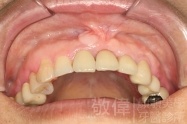

治療前-缺上排前牙   治療後